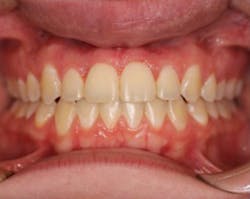

The patient was referred to an orthodontist and, after a comprehensive orthodontic examination, a treatment plan was generated (figure 6). After conventional orthodontic therapy was rendered, the patient was happy with her esthetics, occlusion, and function (figure 7). The patient vowed never again to perform dentistry on herself.